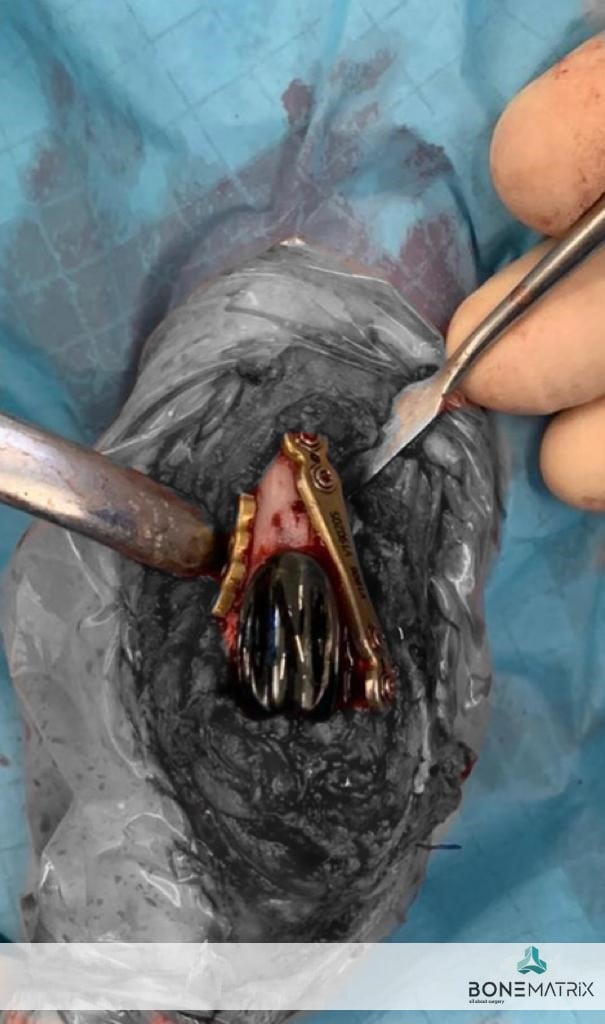

- rotação extrema do joelho

Num cenário de mais que provável amputação, acabamos por ter a sorte de encontrar tutores motivados que quiseram lutar por este membro. Uma cirurgia complexa reparou o que era possível, e um excelente trabalho de reabilitação devolveu a função possível a um membro perdido.